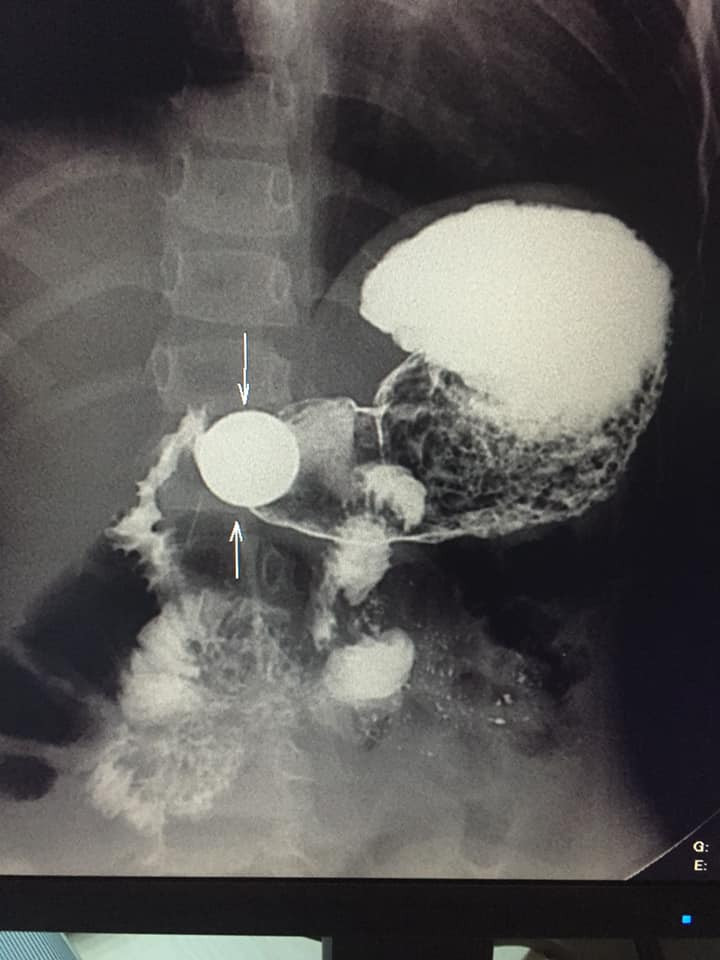

Bakıda azyaşlının mədəsində narahatlıq yarandığı üçün həkimə gətirilib.

Lent.az xəbər verir ki, müayinə zamanı 4 yaşlı uşağın mədəsindən 5 qəpik pul tapılıb. Onun bu problemdən qurtulması üçün endoskopiya olunacağı bildirilir.

Azyaşlının mədəsində tapılan qəpiyin fotolarını təqdim edirik: